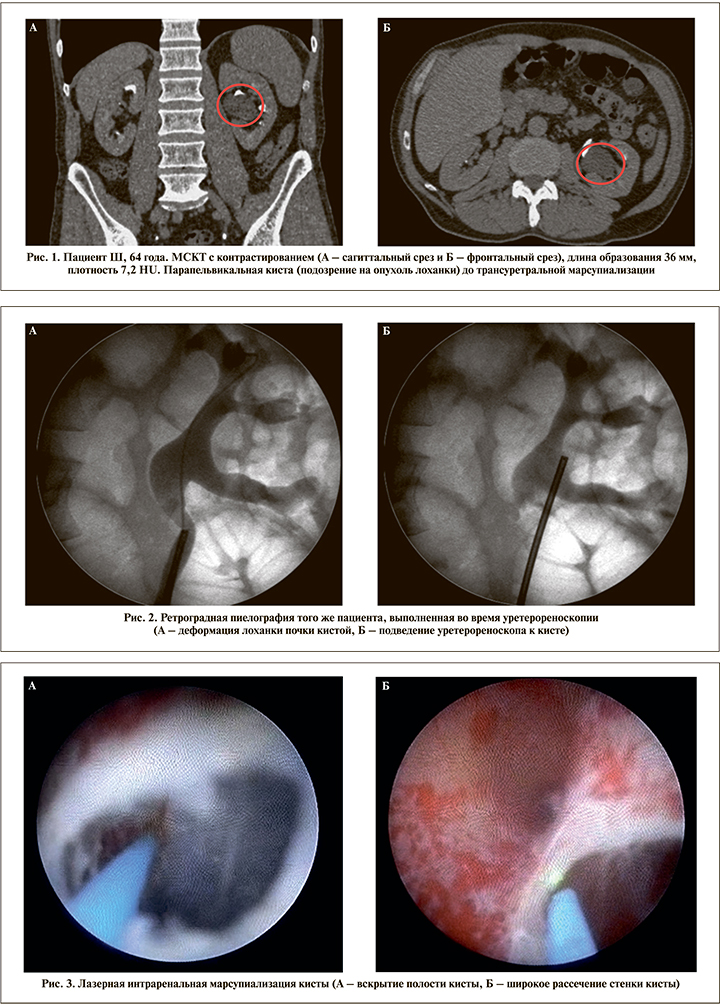

Материалы и методы. С марта 2016 по февраль 2021 г. 9 пациентам (4 мужчины и 5 женщин, возраст – 42–78 лет) с парапельвикальными кистами почек проведена трансуретральная интраренальная марсупиализация, еще 2 пациентам (2 мужчины, возраст – 46 и 52 года) выполнена перкутанная интраренальная марсупиализация с использованием лазерной энергии в отделении малоинвазивной урологии ГКБ им. Д. Д. Плетнёва Москвы. Перкутанная марсупиализация выполнялась во время перкутанной нефролитотрипсии, проведенной по поводу лоханочных камней размером 3,5 и 2,7 см в положении на спине. Основной жалобой пациентов являлась боль в поясничной области на стороне поражения, у 7 (63,6%) пациентов также отмечалась рецидивирующая гематурия. У всех пациентов, включенных в данное исследование, по данным МСКТ с контрастным усилением были определены парапельвикальные кисты размером 3,1±1,8 см, причем у 2 больных образование описано как папиллярная опухоль лоханки. Пиелоэктазия 2,6±1,3 см отмечена у 9 (81,8%) пациентов.

При трансуретральном доступе под эндотрахеальным наркозом вводился ригидный уретероренооскоп диаметром 8 Fr. Выполнялись уретерореноскопия, ретроградная пиелография, при необходимости использовалось интраоперационное УЗИ для уточнения локализации кисты и места рассечения ее стенки (3 пациента). В дальнейшем через рабочий канал проводилось лазерное волокно (365 мкм), выполнялся разрез выступающей в лоханку стенки кисты на всем протяжении и тщательно осматривалась ее полость в белом свете, а также с применением узкоспектровой эндоскопии (NBI-технология, Olympus) или компьютерной хромоэндоскопии (Image1S-технология, Karl Storz). При изменениях внутренней стенки кисты выполнялась «холодная» биопсия. Для дренирования полости кисты интраоперационно устанавливался внутренний мочеточниковый J-J-стент на срок от 4 до 6 нед. (рис. 1–5). При перкутанном доступе интраренальная лазерная марсупиализация парапельвикальной кисты выполнялась после выполнения нефролитотрипсии через нефроскоп диаметром 24 Fr. Помимо нефростомического дренажа пациентам в полость кисты антеградно устанавливался внутренний J-J-стент. Нефростомический дренаж удалялся на 2–3-и сутки после операции, внутренний стент – через 4–6 нед.